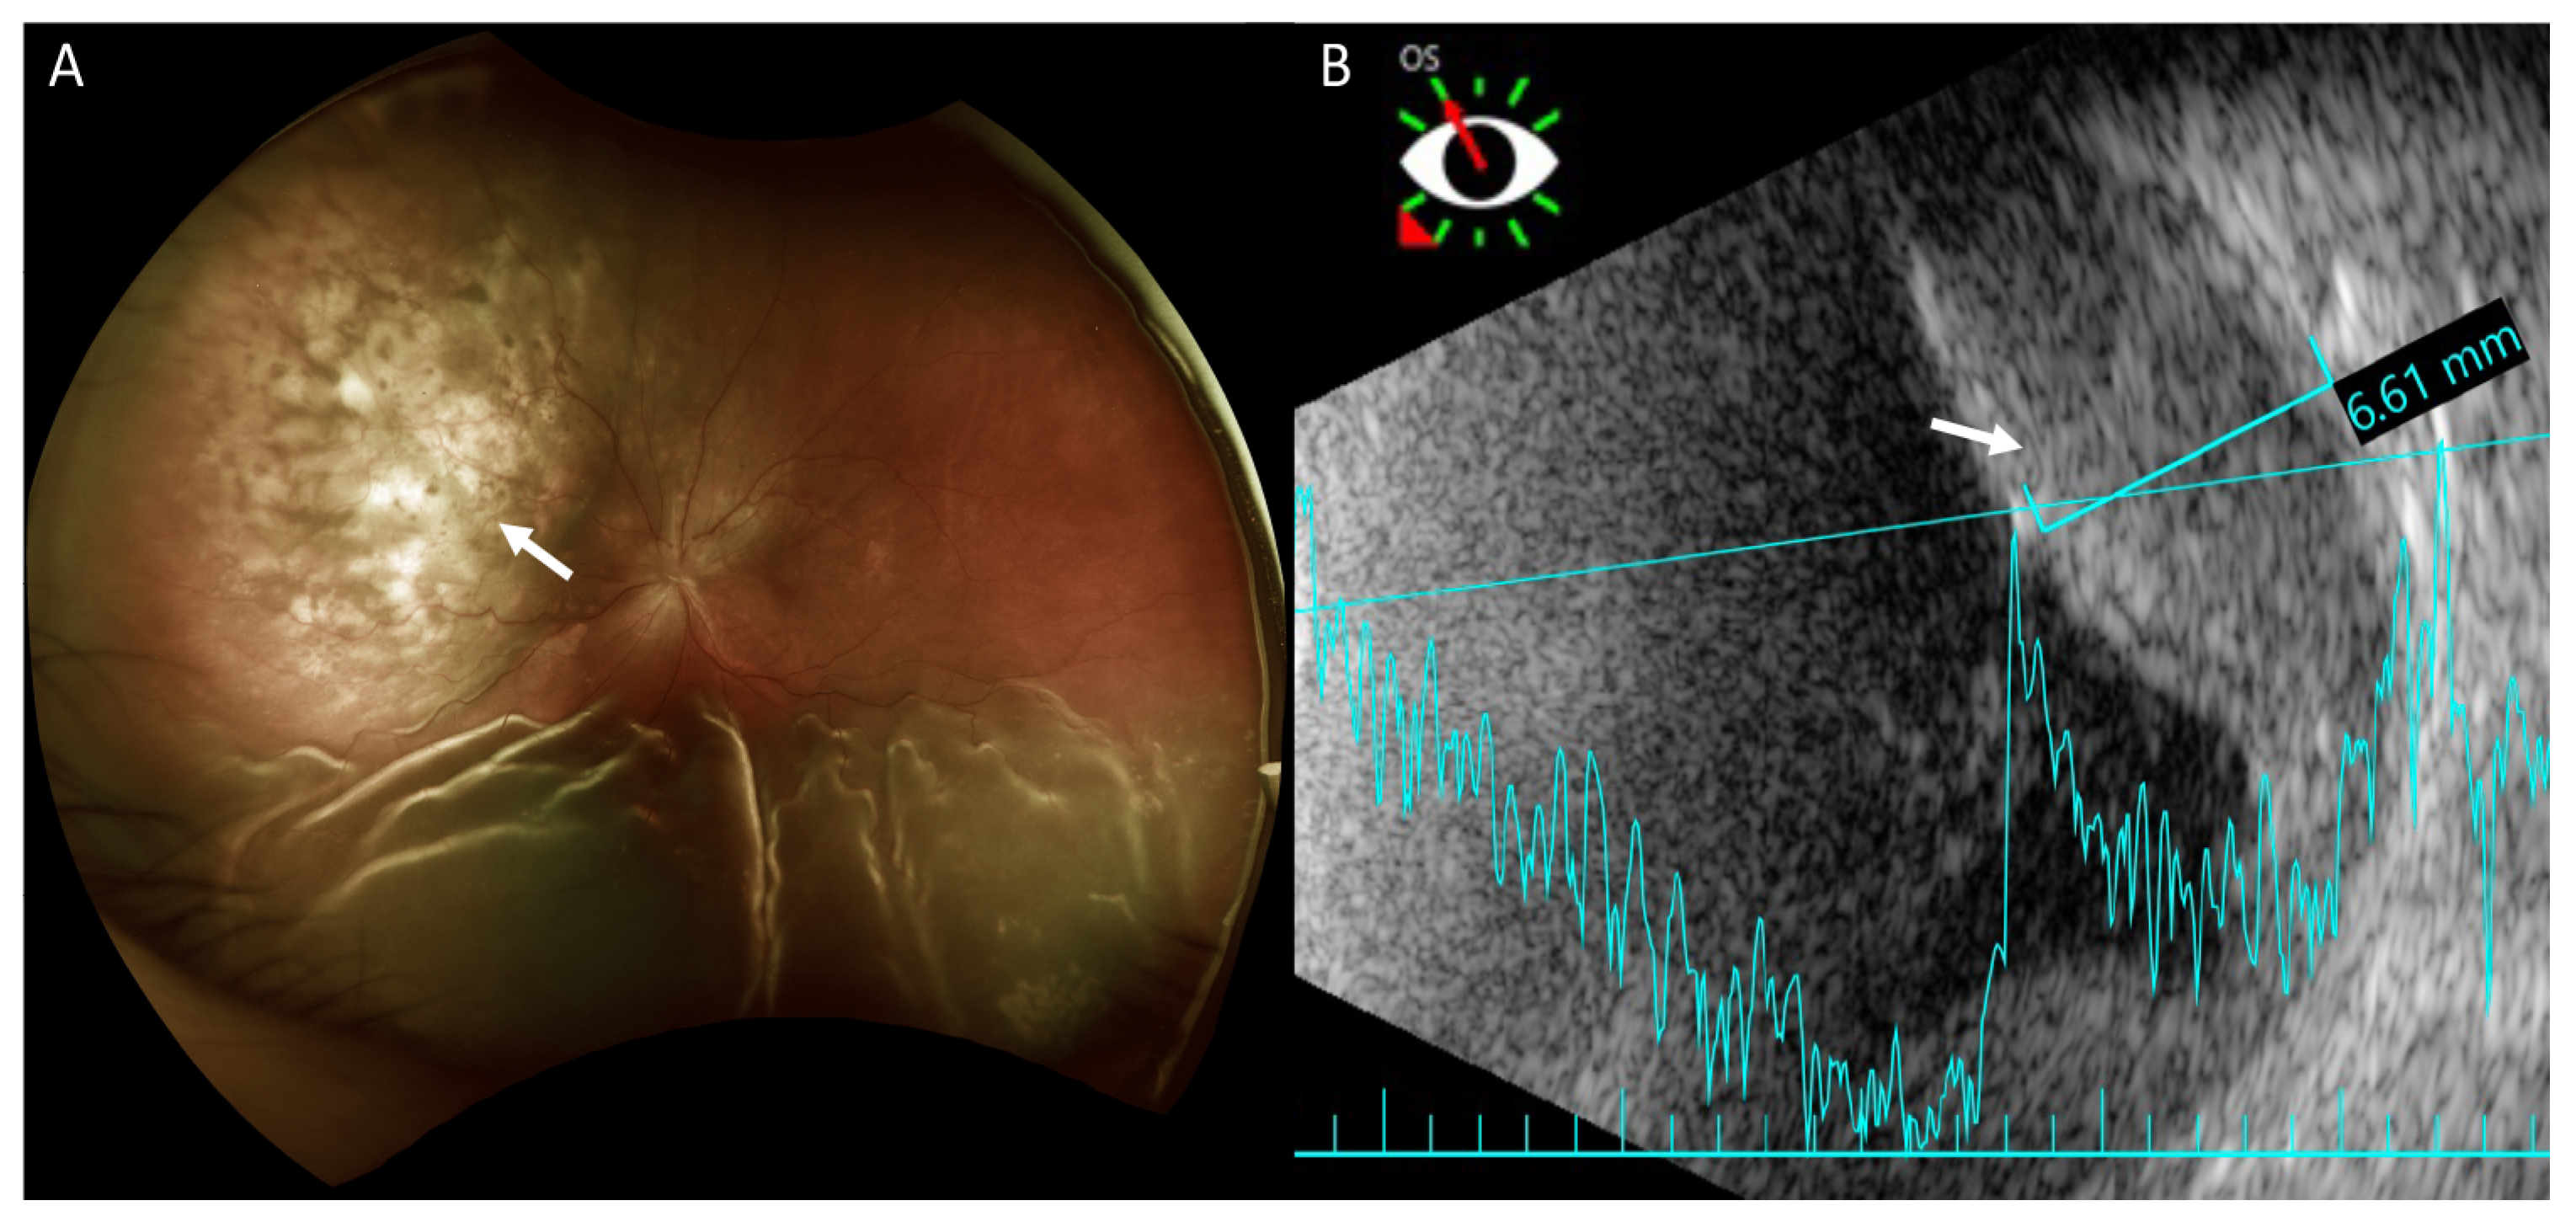

Fundus examination revealed retinal detachment mainly in the inferior region and an amelanotic choroidal mass with retinal detachment in the superior quadrant of her left eye (Figure 2A). Ultrasonography showed that this achromic choroidal mass was a hyperechoic lesion in the subretinal region with a thickness of approximately 6.61 mm, raising the possibility of intraocular tumor or metastasis (Figure 2B).

Figure 2.

Fundus photography and B-scan ultrasonography of the left eye. (A) Fundus photography shows exudative retinal detachment in the inferior retina and an amelanotic choroidal mass in the superior quadrant (arrow) in marked relief. Exudative retinal detachment is seen mainly on the sides of the choroidal mass. (B) Ultrasonography shows the achromic mass in the superior region as a hyperechoic lesion in the subretinal region (arrow) with a thickness of approximately 6.61 mm.

Examinations to support the diagnosis of choroidal metastasis include fundus examination, ultrasonography, FA, ICG, and optical coherence tomography [2]. Furthermore, magnetic resonance imaging of the brain and orbit can rule out any coexisting metastatic brain lesions. On fundus examination, choroid metastases usually appear as solid, spotted, and yellow lesions [10], similar to those observed in the superonasal region in our patient (Figure 2A). Ultrasonography provides the depth and dimensions of the lesion; however, the clinical appearance of choroid metastasis or primary tumors such as melanoma or hemangioma can be similar. Thus, investigating the growth pattern and histoarchitecture of choroid tumors is important, with metastatic tumors being more lobulated and having higher reflectivity than primary choroid melanomas [3]. It was difficult to determine if the choroid tumor was lobulated in our patient because the hyperechoic lesion was situated beneath the ERD. However, the lesion showed high reflectivity. Choroid tumors usually have a similar pattern on FA, with a hypofluorescent pattern in the early phase and heterogeneous hyperfluorescence in the late phase. In addition, pinpoint hyperfluorescence may occur [3]. Thus, it is difficult to confirm if the lesion is a choroid tumor, such as melanoma or choroid metastasis using FA. In our patient, because of ERD, we did not observe a heterogeneously hyperfluorescent pattern in the late phase. ICG could potentially help differentiate choroidal tumors. Early rapid filling with extreme hyperfluorescence within 1 min, and sometimes a late wash-out phenomenon is often present in choroidal hemangioma [11,12]. Choroidal melanoma has varied presentation but usually demonstrates slower filling and less hyperfluorescent intensity compared to choroidal hemangiomas. Visible intrinsic vascularization is seen in 66% of choroidal melanomas, but most are hypofluorescent throughout [12]. Choroidal metastasis usually appears hypofluorescent in all phases [3,12], as seen in our patient.